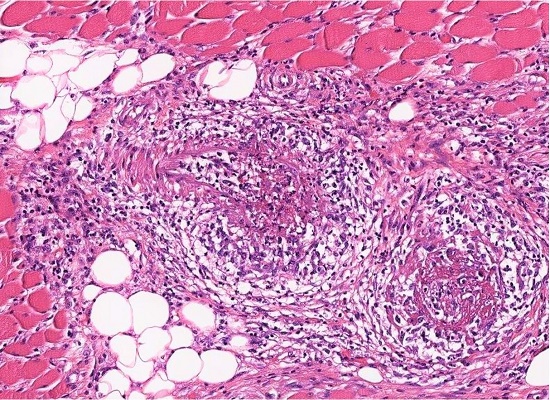

Postmortem examination revealed necrotizing vasculitis in skeletal muscle, (Figure 1 and Figure 2), peripheral nerves, esophagus, stomach, small intestine, pancreas, liver, adrenals, kidneys, lungs and pericardium, involving predominantly medium-sized arteries, but also some large parenchymal arteries in the liver, associated with multifocal thromboses in liver (up to 2 cm), myocardium, thoracic lymph nodes and left adrenal gland, and hemorrhages in left parietal-occipital cerebrum (7 × 6 × 5 cm), upper right arm (29 × 18 cm), stomach, intestines, bladder, pericardium, trachea, mesentery, omentum, right ovary and right breast. In addition to Figure 1 and Figure 2, a virtual (digital) slide of skeletal muscle is available for viewing at the Larry Nichols collection.1 It is case 003.

The next day, the patient reported feeling much better, but that night began having episodes of confusion and delirium. Immunoglobulin therapy was discontinued and trazodone was started. The following day, she remained afebrile and hemodynamically stable. Her oxygen saturation was 98-100%. She appeared comfortable. Her lungs were clear. Her neurological status remained unchanged. The next day, serology for anti-Ro/SSA and anti-La/SSB was negative. The following day, open biopsies of the peroneus brevis muscle and peroneal and sural nerves were performed, which revealed necrotizing vasculitis of vessels in muscle and sural nerve, active and chronic neurogenic muscular changes, epineural fibrosis and chronic axonal loss.